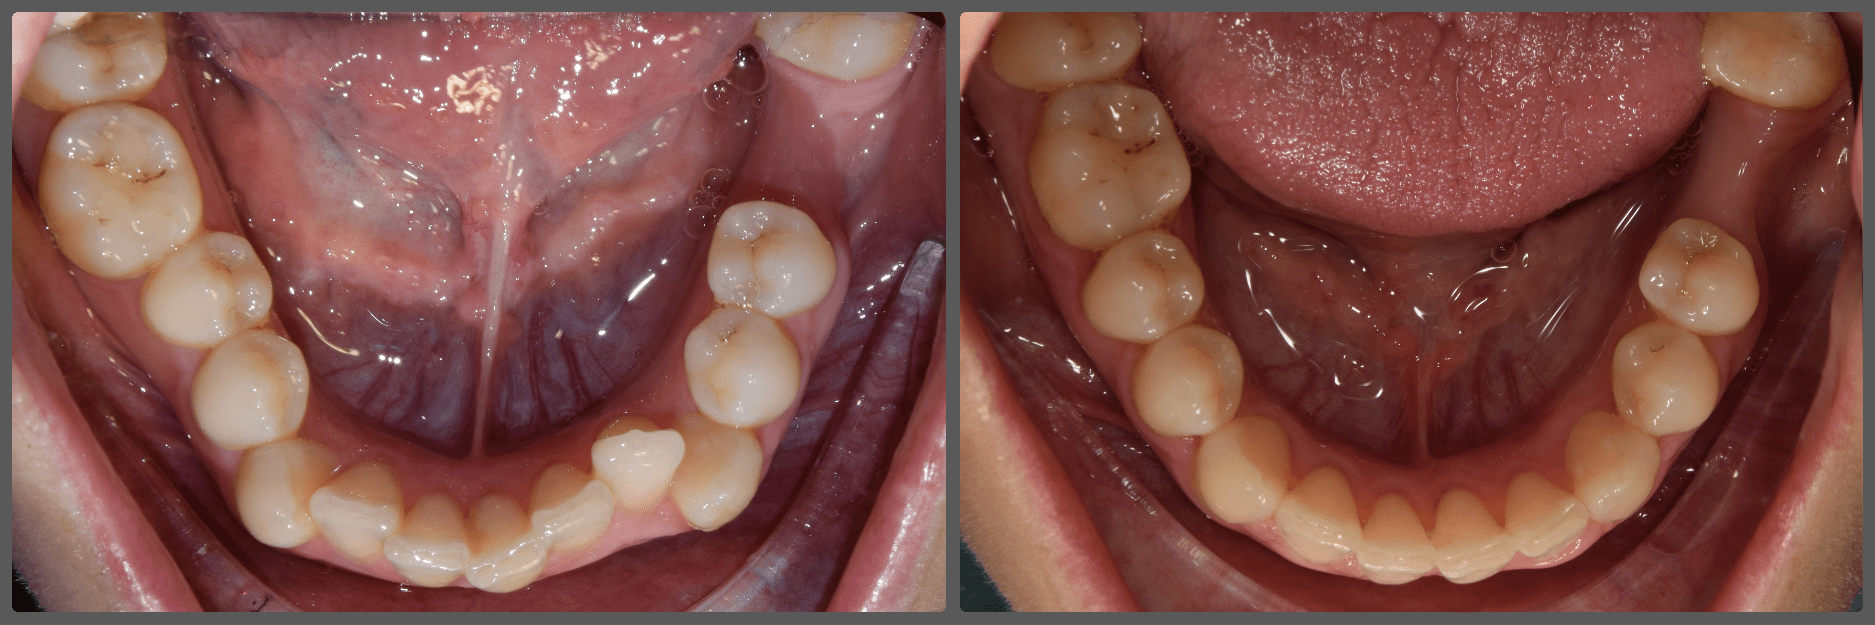

Balázs súlyos alsó torlódása miatt keresett fel magánrendelésemen. A diagnosztikus vizsgálatok során előbbin túl alsó-felső fogívszűkületet, valamint nyitott harapási hajlamot állapítottam meg. Kezelését Pitts21 alsó-felső rögzített fogszabályozó készülékkel kezdtük meg. A nyitott harapási hajlamot a hátsó fogakra helyezett harapásemelővel kontrolláltuk. A torlódott fogaknak tolórugóval és interproximális redukcióval teremtettünk helyet, és intermaxilláris gumihúzással tökéletesítettük a harapást. A fogszabályzó kezelés teljes időtartama alatt Balázs 110%-osan együttműködő volt, ezért 21 hónap alatt sikerült kiemelkedő végeredményt elérnünk.